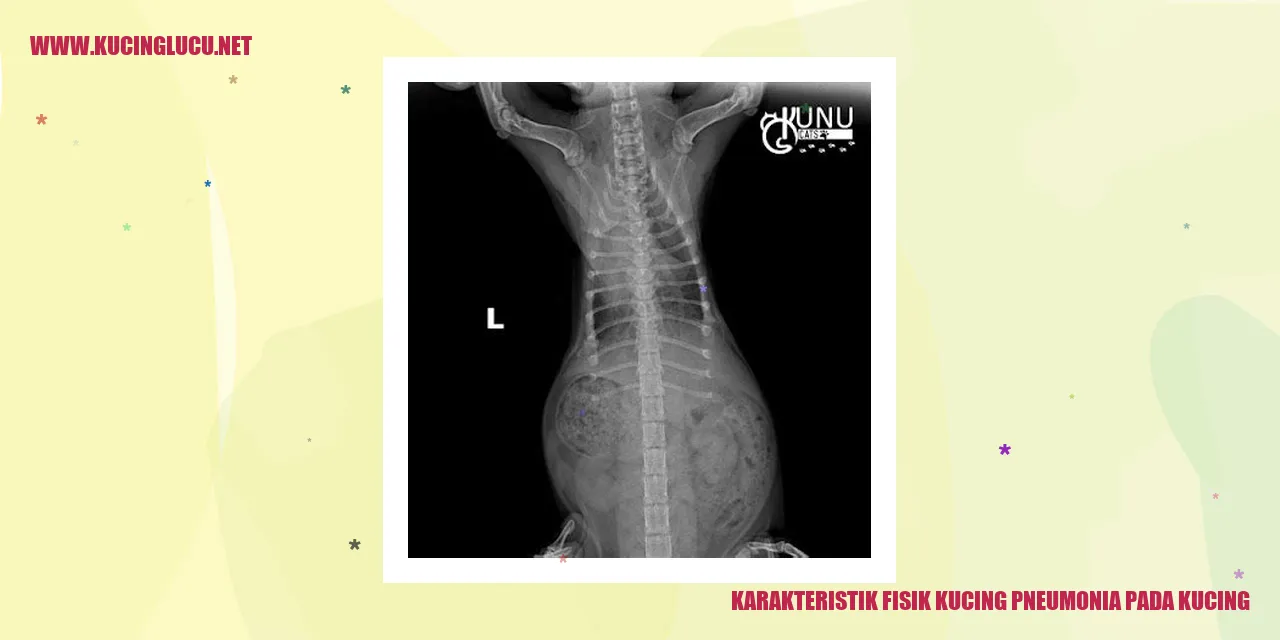

Karakteristik Fisik Kucing Terkena Pneumonia

Pneumonia pada kucing adalah kondisi gangguan saluran pernapasan yang dapat mengenai paru-paru dan sistem pernapasan mereka. Terdapat beberapa ciri fisik kucing yang dapat memberikan petunjuk penting tentang adanya pneumonia pada mereka.

Pertama, kucing yang terkena pneumonia umumnya akan mengalami batuk yang berlarut-larut. Batuk ini dapat terdengar sebagai batuk kering atau batuk dengan produksi dahak yang berlebihan. Selain itu, kucing juga bisa mengalami kesulitan bernapas dan mengeluarkan suara napas yang tidak normal, seperti mengi atau mendengus.

Perubahan pada suara napas juga bisa diamati pada kucing dengan pneumonia. Suara napas yang berat, napas yang terengah-engah, atau bernapas dengan napas yang pendek dapat menjadi tanda-tanda masalah pada sistem pernapasan. Selain itu, kucing juga mungkin menunjukkan kelelahan, lesu, dan kekurangan energi dibandingkan dengan kondisi biasanya.

Kehadiran demam juga dapat mengindikasikan bahwa kucing menderita pneumonia. Jika suhu tubuh kucing melebihi 39°C, ini dapat menjadi pertanda adanya infeksi yang sedang berlangsung. Kurangnya nafsu makan dan penurunan berat badan juga bisa terjadi akibat pneumonia yang dapat memengaruhi kondisi keseluruhan kesehatan kucing.

Sangat penting untuk memerhatikan ciri-ciri fisik ini dan segera membawa kucing ke dokter hewan jika ada kekhawatiran mengenai pneumonia. Kucing yang terkena pneumonia membutuhkan perawatan medis yang tepat guna memulihkan kesehatannya dan mencegah terjadinya komplikasi yang lebih serius.

Pneumonia pada kucing dapat didiagnosis oleh dokter hewan melalui pemeriksaan fisik, analisis darah, sinar-X, ataupun tes tambahan seperti tes dahak atau tes diagnostik lainnya. Hasil pemeriksaan ini sangat penting untuk menentukan penyebab pneumonia serta memberikan pengobatan yang tepat.